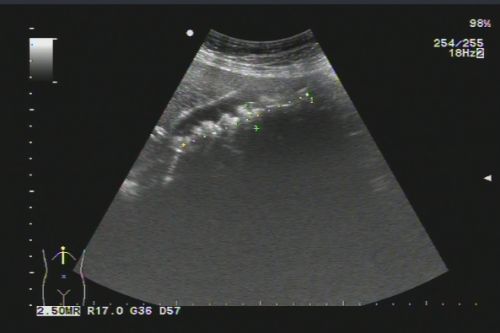

B超看到胆囊内充满结石。